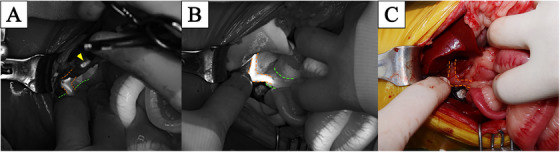

After performing a ventral medial laparotomy, the prolapsed GBM and ruptured gallbladder were identified (Figure 1A). The liver parenchyma adjacent to the gallbladder was so friable that the parenchyma tore spontaneously. After removing the protruded ball‐shaped mucocele with DeBakey forceps, suction was used to evacuate the remaining bile fluid. The ruptured gallbladder was dissected from the right medial and quadrate liver lobes using sterilised cotton swabs and electrocautery, starting from the fundus and proceeding towards the cystic duct. After gallbladder dissection (Figure 1B), ICG was detected using an NIRF imaging machine (Metagenie, MetapleBio, Korea). Under real‐time NIRF ICG, the filling defect in the CBD was easily visualised. When the surgeon gently touched the entire CBD, no firm material was palpable and the visualised filling defect appeared to be mucinous material in the CBD lumen (Figure 2A). External manipulation of the CBD was performed using real‐time ICG. The surgeon grasped the CBD with his fingers and massaged it gently, breaking the mucinous materials and moving them into the duodenum through the major duodenal papilla. The ICG‐filling defect in the CBD had resolved with ICG present throughout the entire CBD (Figure 2B,C). Due to the patency of the CBD being assessed with flow of ICG, direct CBD catheterisation either normograde via choledochotomy or retrograde via duodenotomy, was deemed necessary. After ligation of the cystic duct and artery with two non‐absorbable, polymer locking clips, cholecystectomy was performed (Fisher et al. ref. 2022). Liver biopsy of the left lateral lobe was performed using a guillotine suture (Figure 1C). Abdominal lavage with warm Hartmann’s solution greater than 200 mL/kg was conducted, followed by Jackson‐Pratt drain placement. Conventional closure of the abdomen, subcutaneous sutures and skin sutures were performed.